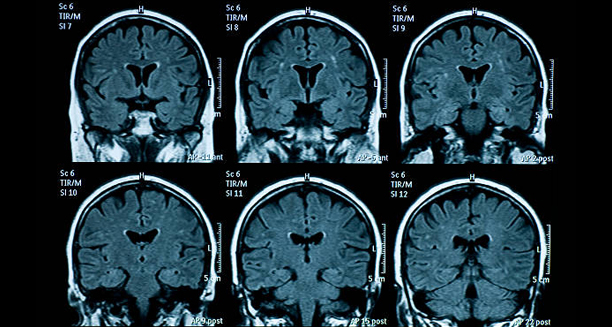

4. Imaging Tests

MRI or CT scans of the brain may be ordered to exclude other serious conditions such as:

- Brain tumours

- Vascular malformations

- Infections or inflammation

Imaging is especially important in first-time or atypical cases.